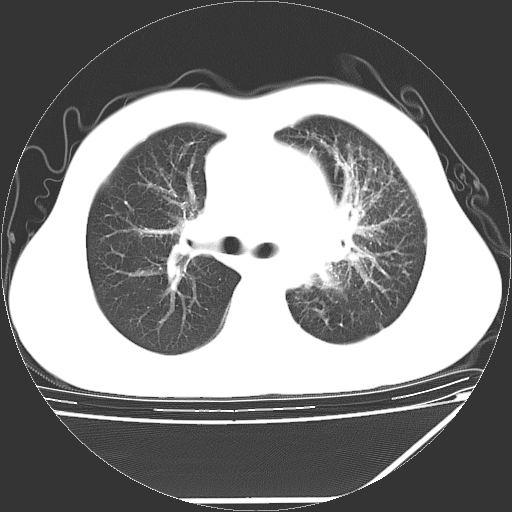

男,13岁,咳嗽、咳痰伴发热一周。

中上纵隔见多枚淋巴结肿大,部分相互融合成团片,左肺门增大,上叶支气管变窄,肺内多处斑片状 索条状及棉絮状致密影。临床“男,13岁,咳嗽、咳痰伴发热一周。”首先考虑:原发综合征!不除外淋巴瘤可能!

纵隔多发肿大淋巴结,部份有融合改变。双肺血管气管束增厚,以肺门为中心向外周散发,以左肺下叶为明显。考虑淋巴瘤可能性大。不除外原发综合征。

中上纵隔见多枚淋巴结肿大,部分相互融合成团片,左肺门增大,上叶支气管变窄,左肺支气管血管束增粗,可见磨玻璃样影。临床“男,13岁,咳嗽、咳痰伴发热一周。”首先考虑:淋巴瘤可能性大!

左肺野见淡片状影,病因整体多考虑结核

单纯看片子感觉左侧肺通气不畅,而不像肺内病变引起的纵隔病变。而且纵隔及左肺门都有淋巴结增大。首先还是考虑一下结节病,不排除淋巴瘤!!!